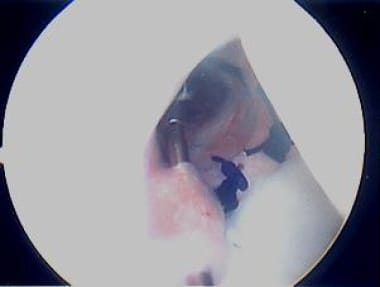

The images below show posterior plication and are representative. The view is of a left shoulder from the anterosuperior portal, just anterior to the biceps long head, aimed in a posteroinferior direction. The patient is in the lateral decubitus position, with the arm in 5 lb of traction, positioned in 45° of abduction and 20° of forward flexion. The working portal is the typical posterior portal, which is 1.5 cm inferior and 1.5 cm medial to the posterior corner of the acromion.

First, a suture passer device (Spectrum; ConMed Linvatec, Largo, FL) is placed through the working cannula; next, it is initially passed through a pinch of posterior capsule 1 cm from the labrum and then through the posterior labrum itself (see the image below).

Suture passer device (Spectrum; ConMed Linvatec, Largo, FL) is placed through working cannula, then through "pinch" of posterior capsule, and also through posterior labrum. Photo courtesy of Daniel C Wnorowski, MD.